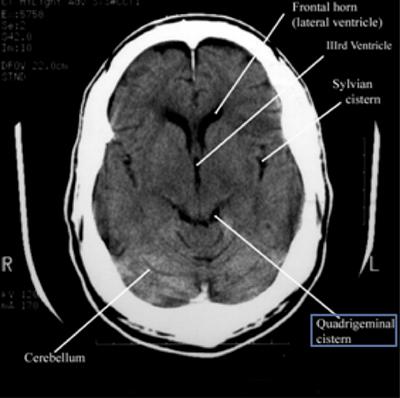

Step 2: Cisterns

Cisterns

Cisterns are the compartments within any of the openings in the subarachnoid space of the brain filled with cerebrospinal fluid. Two key questions to answer regarding the four key cisterns (Circummesencephalic, Suprasellar, Quadrigeminal and Sylvian)

• Is there blood?

• Are the cisterns open?